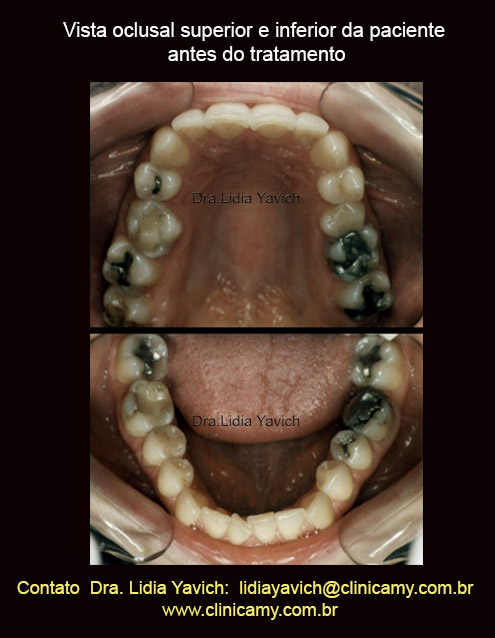

Vista oclusal superior e inferior da paciente no dia da consulta.

Vista oclusal superior e inferior da paciente no dia da consulta.

Os incisivos superiores e inferiores mostram sinal de desgaste.